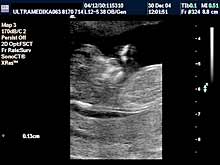

C) III trimestar trudnoće

od 24. do 40. nedelje trudnoće

Indikacija za ultrazvučni pregled:

- Procena funkcije bubrega, organa abdomena, srca i cirkulacije likvora

u mozgu.

Napomena: Na svakom pregledu do kraja trudnoće.

- Procena posteljice i protoka pupčanika, kao i njegov tok i položaj.

Napomena: mogućnost pogrešnog položaja pupčanika na posteljici,

njegovo prednjačenje u porođaju, ili njegov neadekvatan položaj oko

dela tela ploda, ili formiranje čvora ili zapušenje, su krucijalna

informacija u toku pregleda do tada normalne trudnoće.